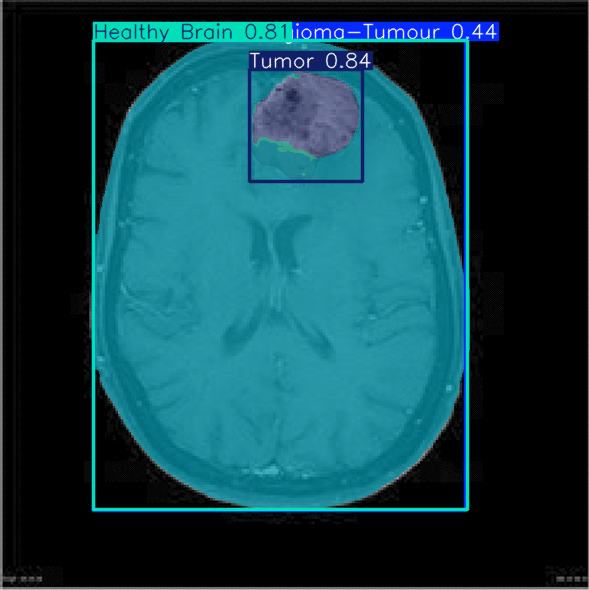

Brain Tumor Segmentation

Medical AI

Pixel-level segmentation of Glioma, Meningioma, and Pituitary tumors from MRI scans using YOLO architectures. The system assists radiologists by highlighting tumor regions with high precision.